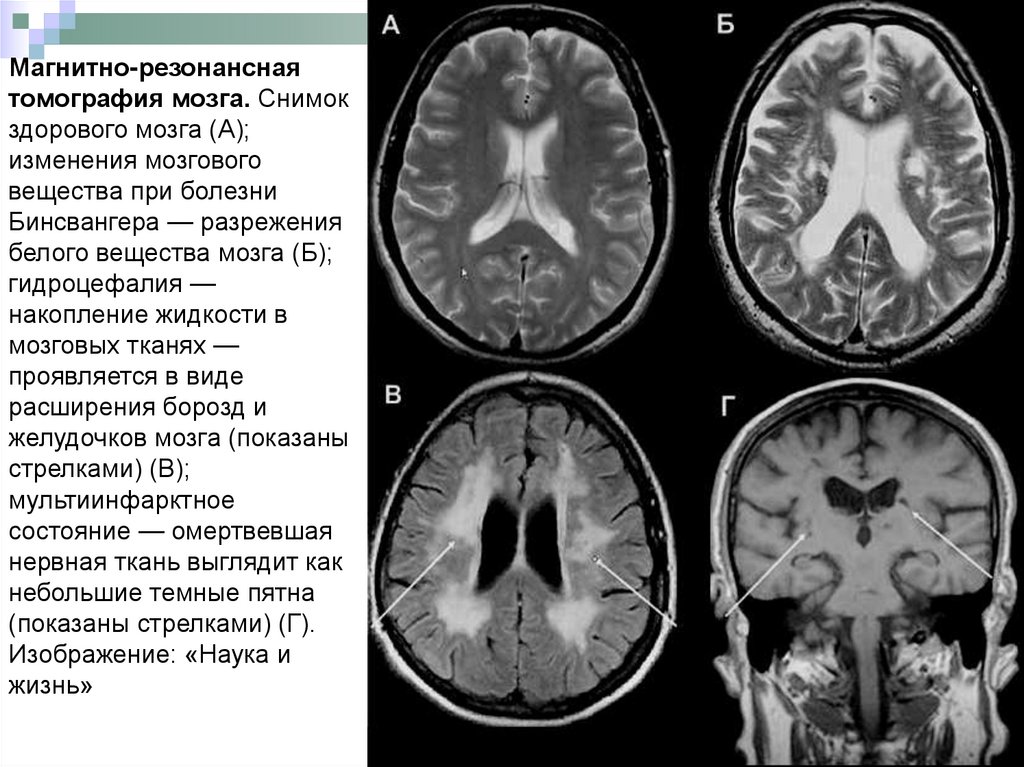

Магнитно-резонансная

томография мозга. Снимок

здорового мозга (А);

изменения мозгового

вещества при болезни

Бинсвангера — разрежения

белого вещества мозга (Б);

гидроцефалия —

накопление жидкости в

мозговых тканях —

проявляется в виде

расширения борозд и

желудочков мозга (показаны

стрелками) (В);

мультиинфарктное

состояние — омертвевшая

нервная ткань выглядит как

небольшие темные пятна

(показаны стрелками) (Г).

Изображение: «Наука и

жизнь»